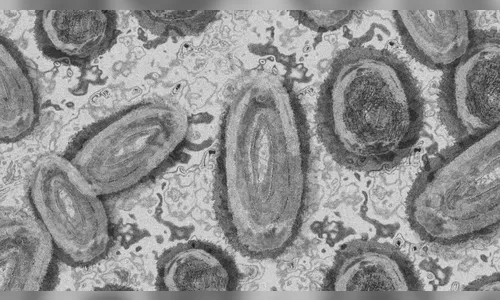

A varíola dos macacos é uma doença causada por vírus e transmitida pelo contato próximo/íntimo com uma pessoa infectada e com lesões de pele.